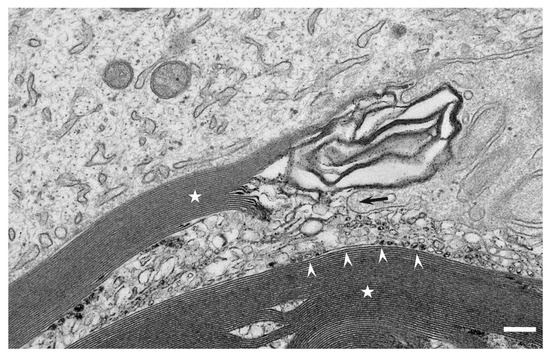

Myelin phagocytosis by macrophages has been an essential feature of demyelinating diseases in the central and peripheral nervous systems, including Guillain–Barré syndrome (GBS), chronic inflammatory demyelinating polyneuropathy (CIDP), and multiple sclerosis (MS). The discovery of autoantibodies, including anti-ganglioside GM1 antibodies in the axonal [...] Read more.

Myelin phagocytosis by macrophages has been an essential feature of demyelinating diseases in the central and peripheral nervous systems, including Guillain–Barré syndrome (GBS), chronic inflammatory demyelinating polyneuropathy (CIDP), and multiple sclerosis (MS). The discovery of autoantibodies, including anti-ganglioside GM1 antibodies in the axonal form of GBS, anti-neurofascin 155 and anti-contactin 1 antibodies in typical and distal forms of CIDP, and anti-aquaporin 4 antibodies in neuromyelitis optica, contributed to the understanding of the disease process in a subpopulation of patients conventionally diagnosed with demyelinating diseases. However, patients with these antibodies are now considered to have independent disease entities, including acute motor axonal neuropathy, nodopathy or paranodopathy, and neuromyelitis optica spectrum disorder, because primary lesions in these diseases are distinct from those in conventional demyelinating diseases. Therefore, the mechanisms underlying demyelination caused by macrophages remain unclear. Electron microscopy studies revealed that macrophages destroy myelin as if they are the principal players in the demyelination process. Recent studies suggest that macrophages seem to select specific sites of myelinated fibers, including the nodes of Ranvier, paranodes, and internodes, for the initiation of demyelination in individual cases, indicating that specific components localized to these sites play an important role in the behavior of macrophages that initiate myelin phagocytosis. Along with the search for autoantibodies, the ultrastructural characterization of myelin phagocytosis by macrophages is a crucial step in understanding the pathophysiology of demyelinating diseases and for the future development of targeted therapies. Full article